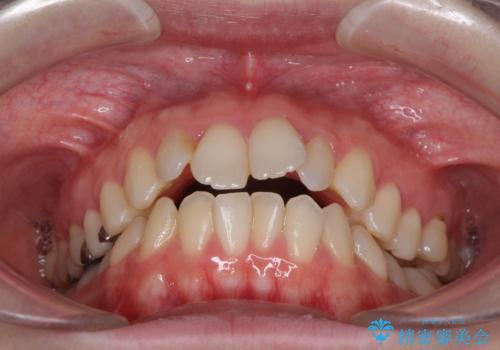

- 前歯のデコボコを気にして来院された患者様です。

下顎が骨格的にずれており、上下正中を合わせることは難しいことが予想されたため、デコボコの解消を主目的として、ワイヤー矯正を行うこととしました。

治療途中で出産されたこともあり、当初予定よりも終了までに期間がかかってしまいました。

舌を前方に突出する癖があったため、上下前歯がなかなか接触しなかったことも治療期間が伸びた要因です。